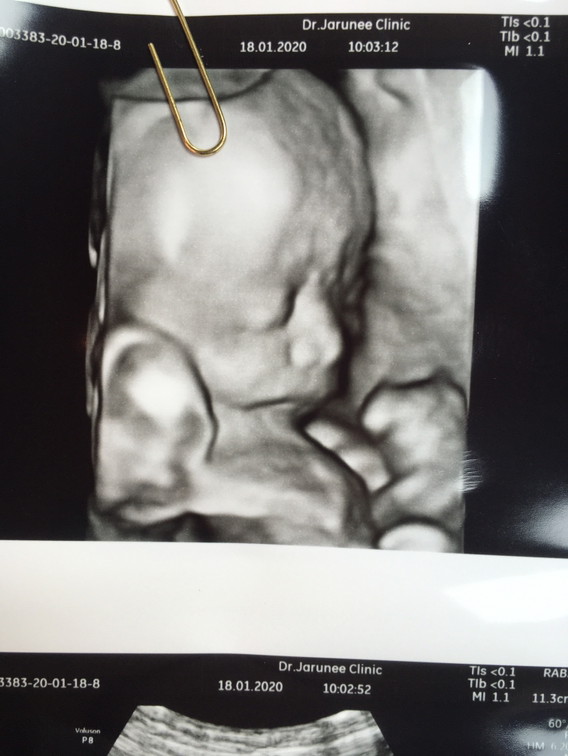

ตอน12wค่าา